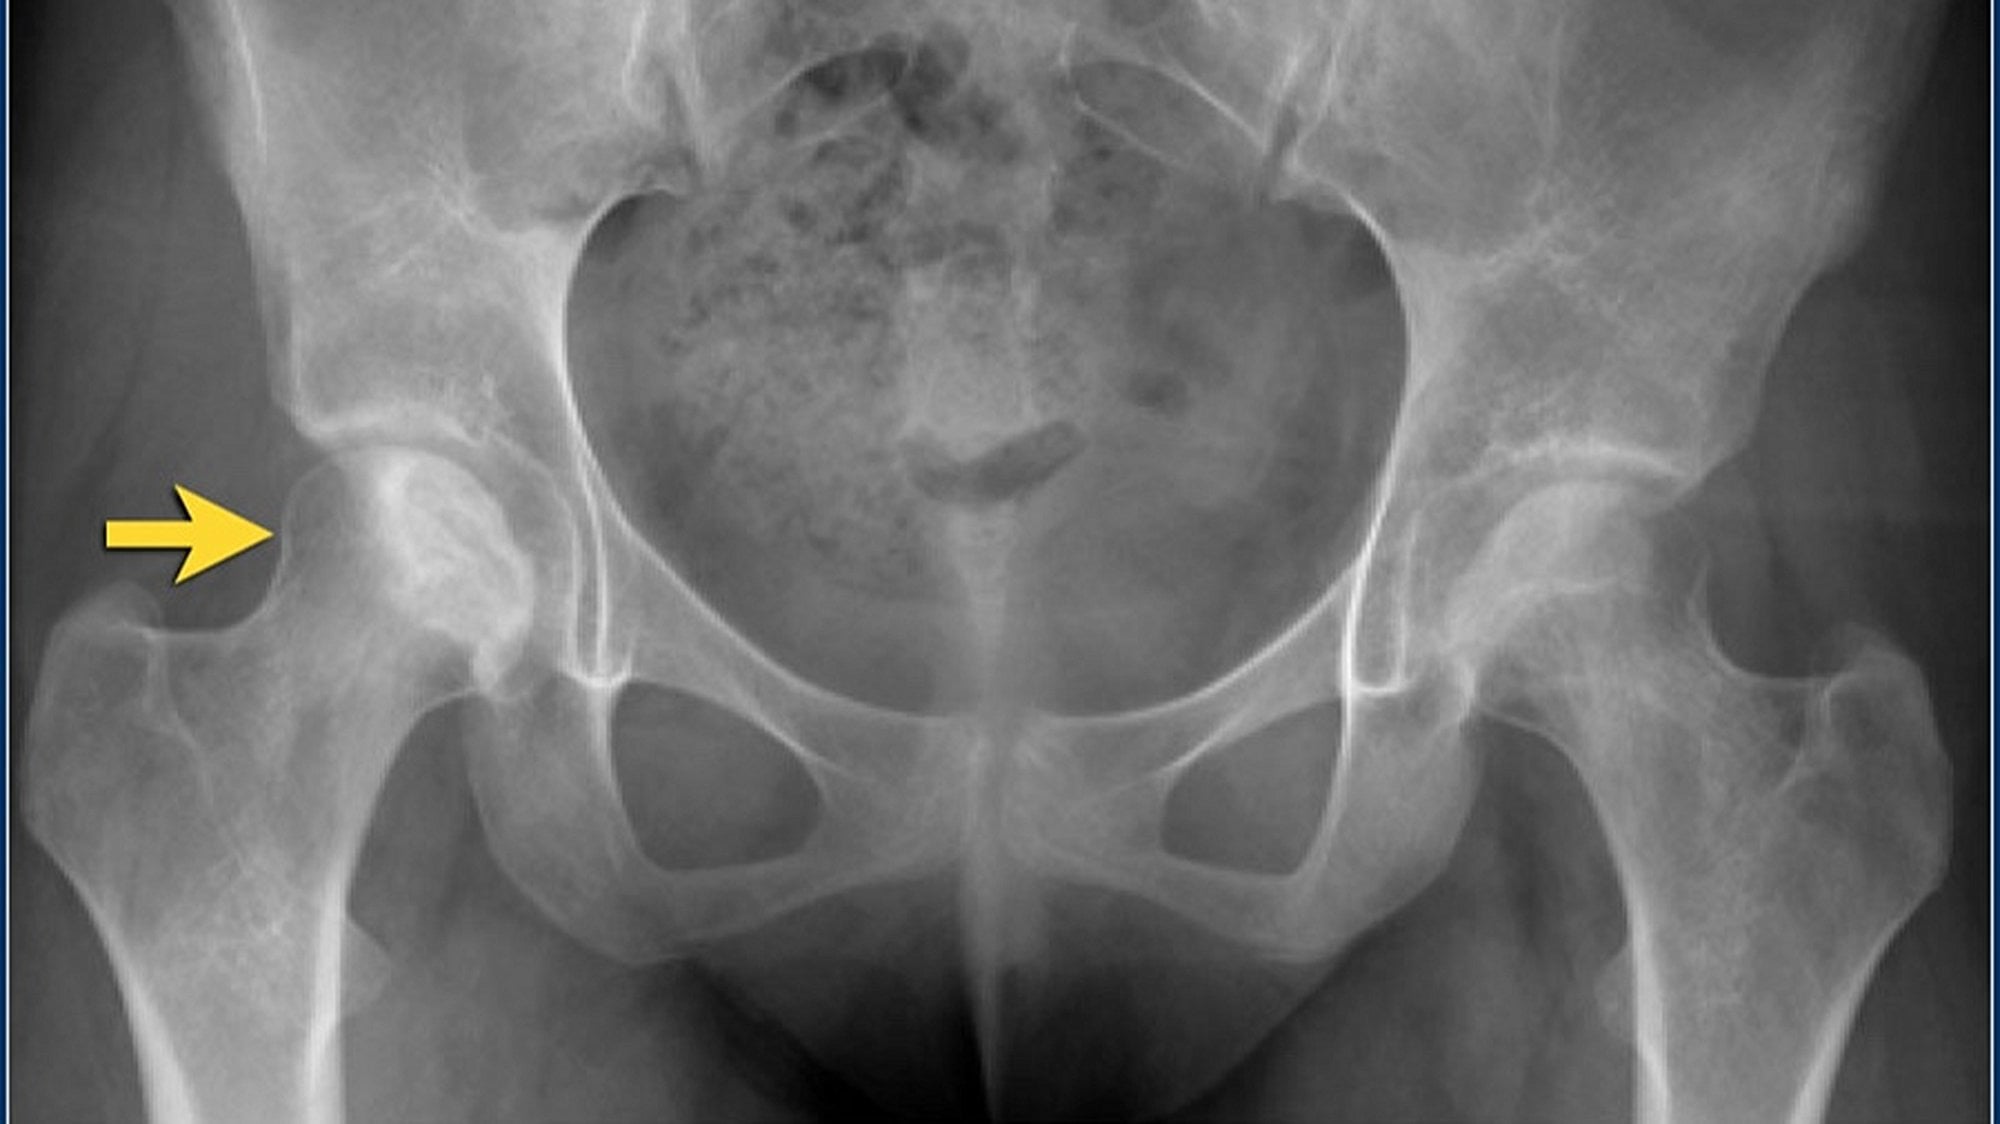

Radyografi

Avasküler Nekroz'un erken evrelerinde düz radyografik bulgular dikkat çekici değildir. Bununla birlikte, Amerikan Radyoloji Koleji, kalça ağrısı ile başvuran Avasküler Nekroz riski taşıyan hastalarda pelvis röntgenini en uygun başlangıç görüntüleme çalışması olarak görmektedir. Bu projeksiyonlardan sadece birinde eklem çökmesi veya kortikal çöküntü görülebileceğinden, hem pelvisin ön-arka görünümü hem de kalçanın kurbağa bacağı lateral görünümü gereklidir.

Hafif-orta Avasküler Nekroz'da radyografiler skleroz ve kemik yoğunluğundaki değişiklikleri gösterir. İlerlemiş hastalıkta düzleşme, subkondral radyolüsent çizgiler (hilal işareti) ve femur başının çökmesi gibi kemik deformiteleri belirgindir.